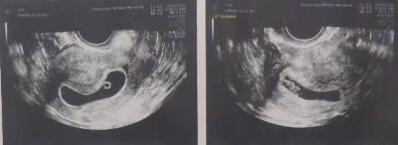

也许是心态放松了,2019年9月移植2个优质卵裂胚胎后,验孕日HCG数值975mIU/ml,张宏展医生交待小花按时回医院做一超、二超、三超,孕期多注意放松身心……